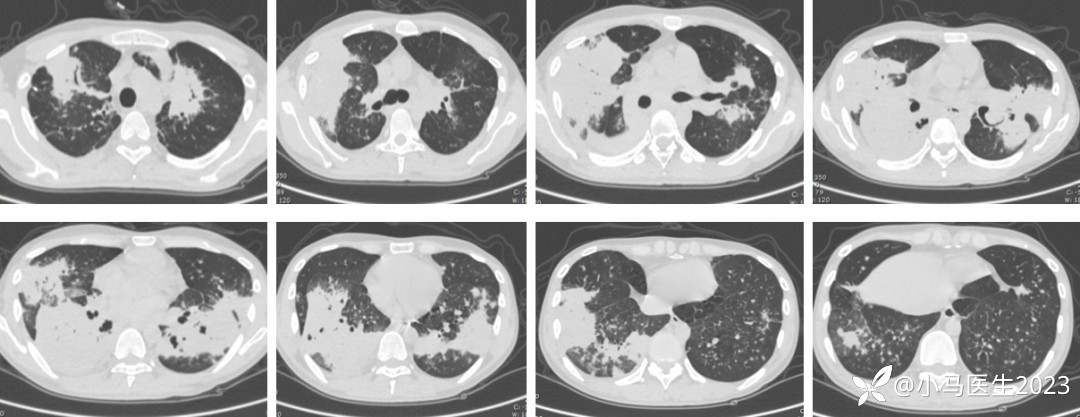

03-29复查胸部CT进展

胸部CT对比

体温不降,氧合不佳,复查CT病灶进展

04-06 胸部CT仍进展

2021-04-28胸部CT进展,空洞形成

胸部CT表现

吸入/淋巴道传播

下肺分布优势

累及双肺,多叶段分布

实变、磨玻璃、粟粒细节、网格结节等

胸膜增厚,胸腔积液

与结核极易混淆!